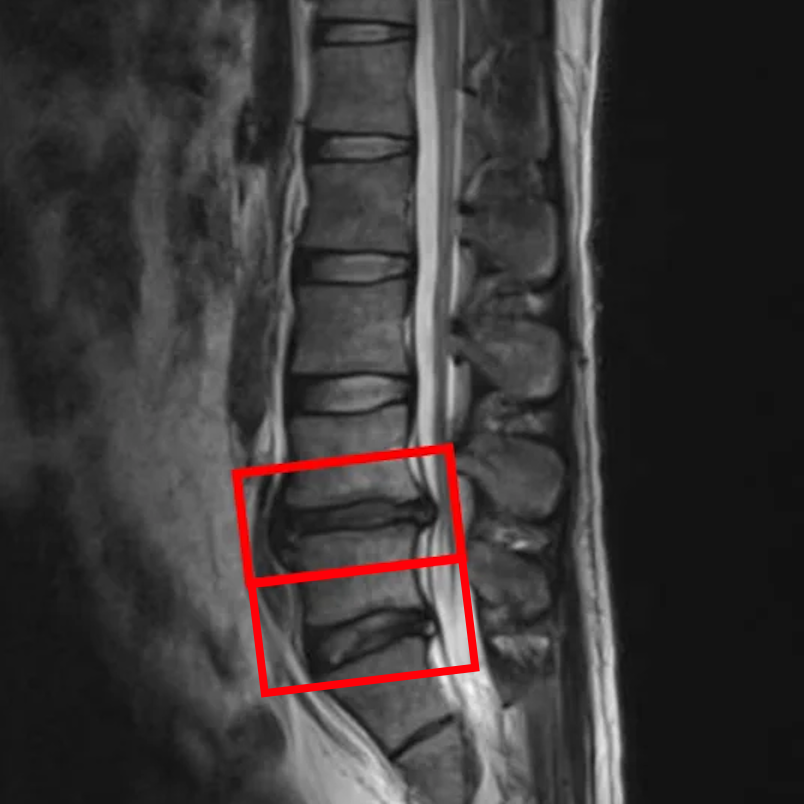

По данным МРТ и результатам осмотра пациента выявлена грыжа межпозвоночных дисков L4/L5, L5/S1, а также стеноз позвоночного канала и межпозвоноковых отверстий L4/L5.